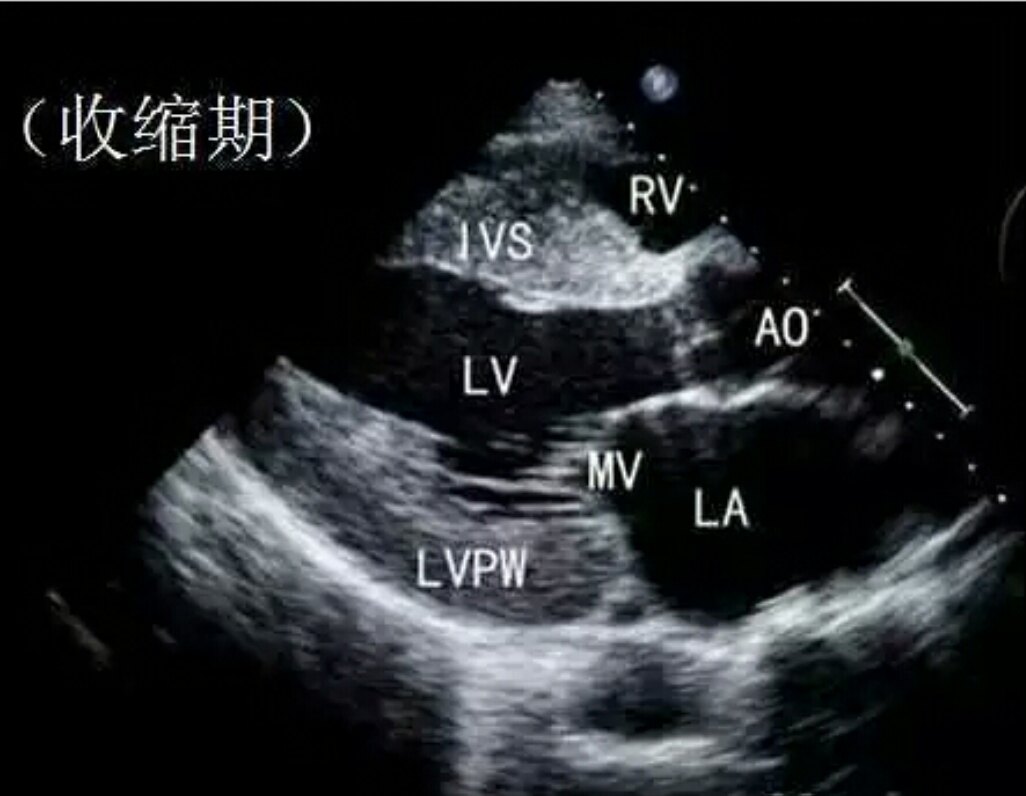

而冠心病呢,听起来就有点吓人,对吧?它是因为心脏的血管堵了,血液供应不上,心脏就会缺血,严重的时候甚至会导致心绞痛或者心肌梗死。想象一下,那种胸口被紧紧抓住的感觉,真是让人窒息。

虽然它们都是心脏的问题,但表现和处理方式却大不相同。高血压需要通过药物控制血压,而冠心病则可能需要血管扩张或者支架植入等更直接的治疗。